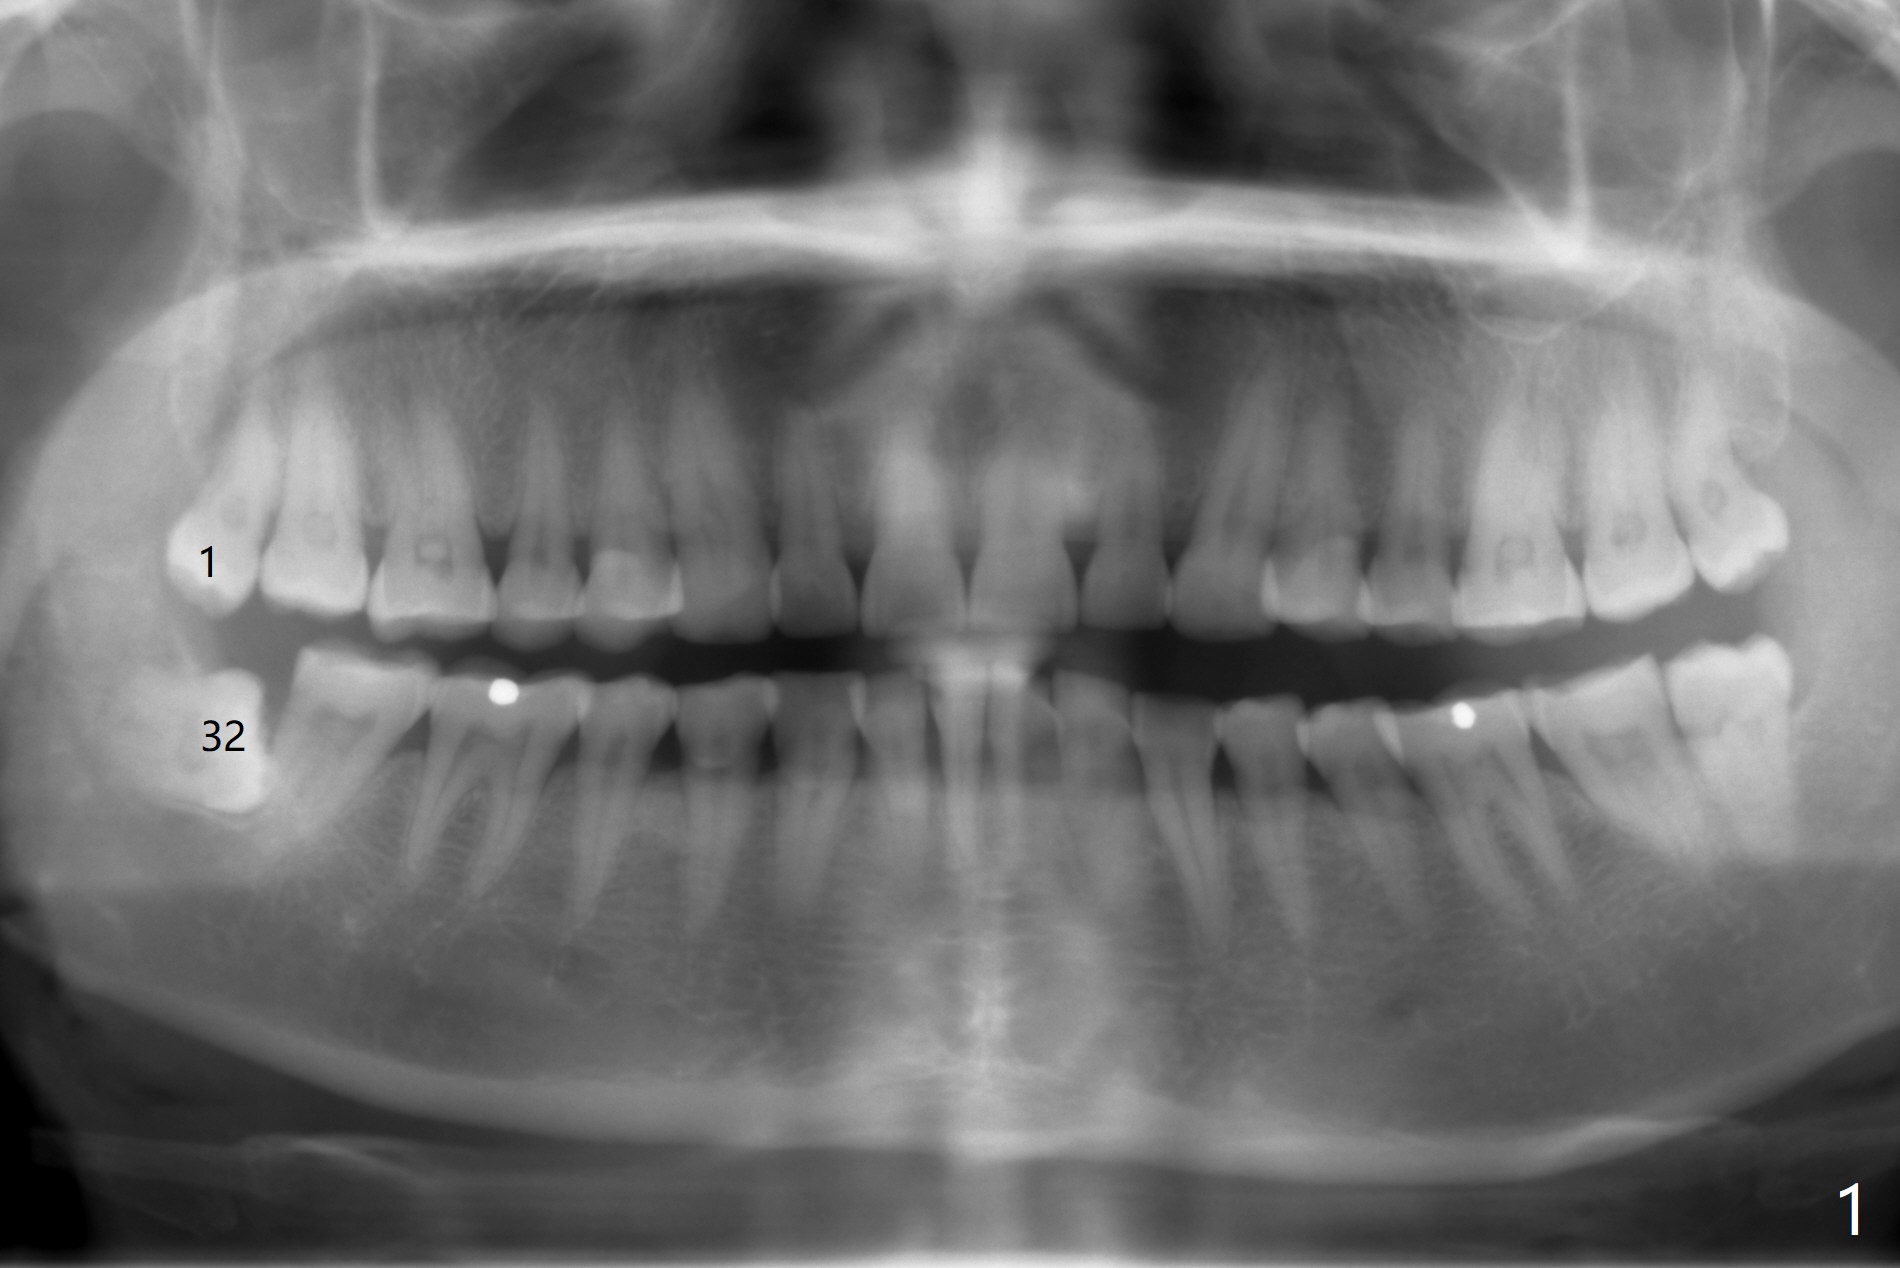

A 47-year-old woman agrees to have #1 and 32 extracted 4 years after X-ray was taken (Fig.1). What is the best method and material to repair the bony defect distal to #31? Steven: Sticky bone. Robert: extract #31 (if mobile) and 32 with #31 implant, bone graft.